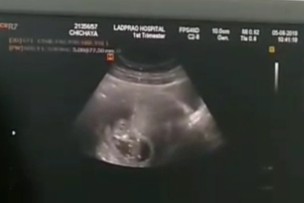

12weekค่ะ ซาวด์วันนี้สดๆร้อนๆจ้า😘✌🏼

ของบ้านนี้จ้า 11+2วีค ปัจจุบัน 32+6จ้า

ตอน 13w ค่ะ ตอนนี้ได้ 28+4wแล้วค่ะ

ภาพตอน10wจ้า ตอนนี้15+4แล้วจ้า

บ้านนี้ตอน 11+3 ปัจจุบัน 30+2 คะ

9วีคเอง ซาวด์ครั้งแรกจ้า❤

จำไม่ผิดน่าจะ 10 w

10+5wตอนนี้31wแล้วค้ะ